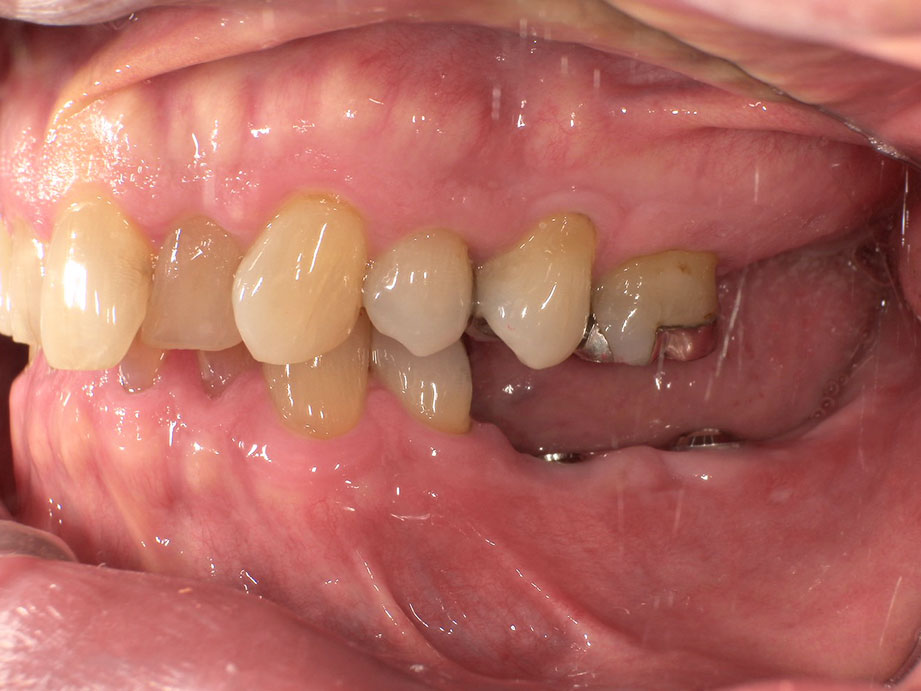

横から見た写真です。